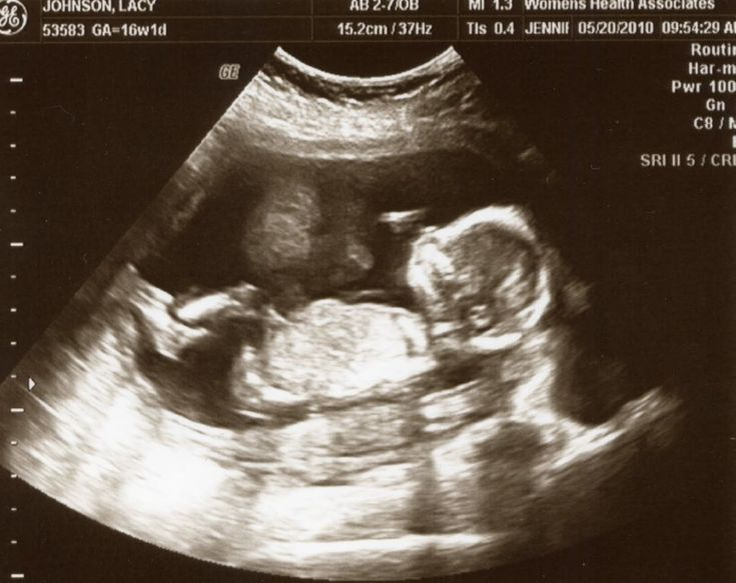

Шевеления во многом зависят от размеров и темперамента будущего малыша. Отчетливо движения малыша можно увидеть на УЗИ, при этом малыш активно двигается, у него отлично различимы все части тела и даже выражения личика. В этом сроке может также узнать, кто живет в вашем животике – девочка или мальчик. В 16 недель вполне точно можно определить пол.

Плод в 16 недель беременности может достигать размеров от темени до копчика в 10-11 см, весит до 120 г, можно сравнить его размер с авокадо. У него укрепляются косточки, ножки активно растут в сравнении с ручками, и он уже активно толкается ими в стенки матки. На крохотных пальчиках сформировались ноготки, малыш может вертеть головкой из стороны в сторону.

Глазки и ушки на лице приближаются к своему окончательному положению. Сердце ребенка работает активно, перекачивая в теле малыша до 25 л крови за сутки. Печень начинает брать на себя функции органа пищеварения, а не кроветворения, постепенно начинает включаться в работу кишечник, проводя пока тренировочные движения.